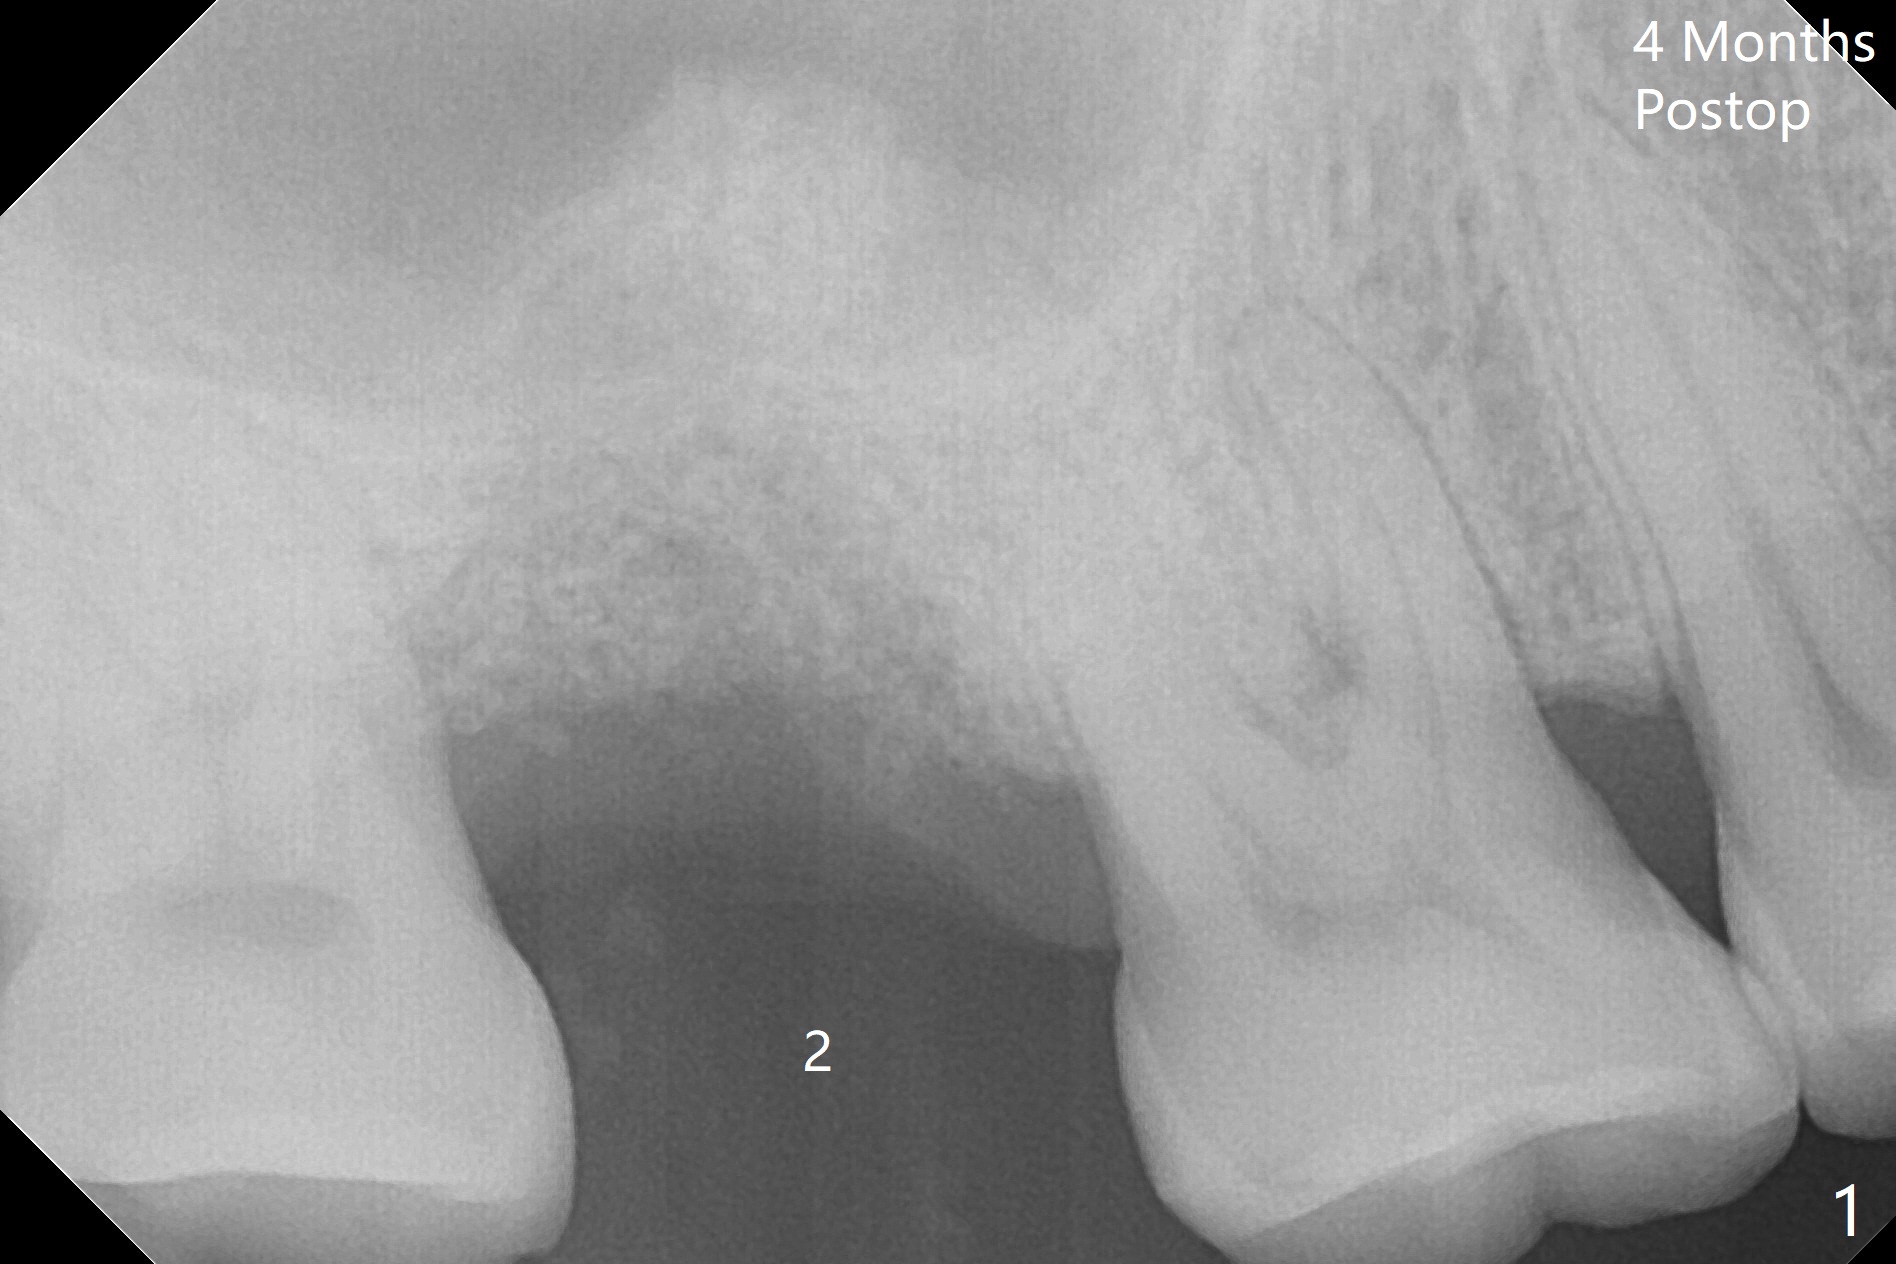

Not long postop, the patient called saying that #2 provisional had dislodged. Due to his busy schedule and coronavirus outbreak, he returns nearly 4 months postop. The abutment is distalized and loose with the underlying implant (5x9 mm). The latter is removed before local anesthesia (Fig.1 distal defect). After initial debridement, a 2.2x13 mm drill is used with a guide of 12 mm offset, followed by insertion of a 4.5x11 mm dummy implant with barely stability (Fig.2). A 5.5x9 mm is placed free hand initially, followed by guide with stability. But the implant has uncovered threads distolingual. Thorough debridement reveals that the sinus membrane has a small perforation. After placement of a piece of Osteogen plug, cortical chip and Vanilla hydrated with .25 cc of GEM21S is packed into the site with a condenser (Fig.3,4). The graft is fixed in place with Perio glue, followed by a piece of GEM Cap with the glue. Three to 4 months later, take CT for healing confirmation. Try to place a shorter implant (e.g., 5x7 mm) without getting into the sinus to reduce infection. In fact the Cap does not stay in place with loss of bone graft (8 days postop).